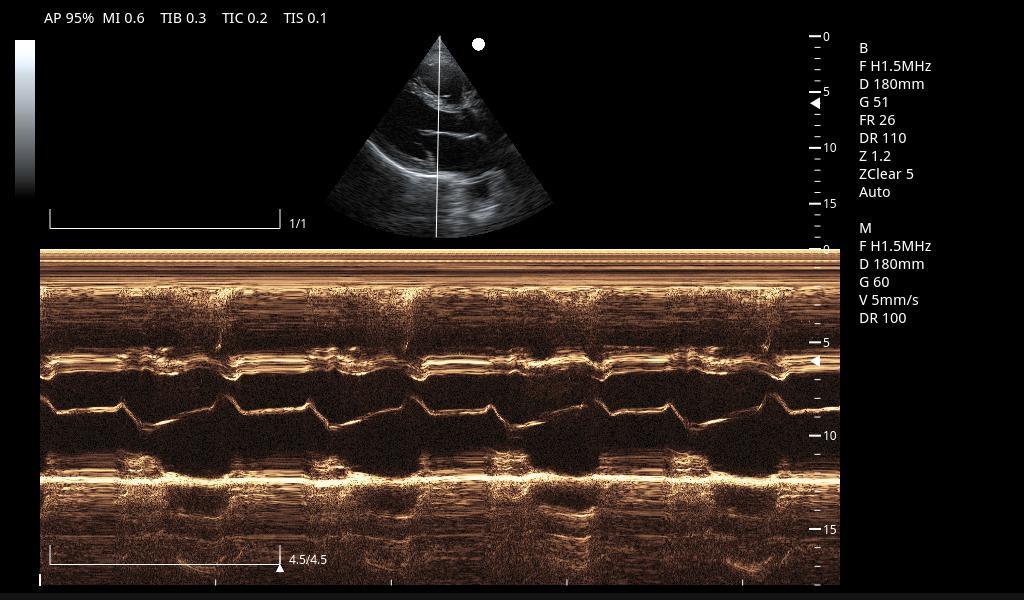

Excelentes imágenes clínicas

|

|

|

|

|

|